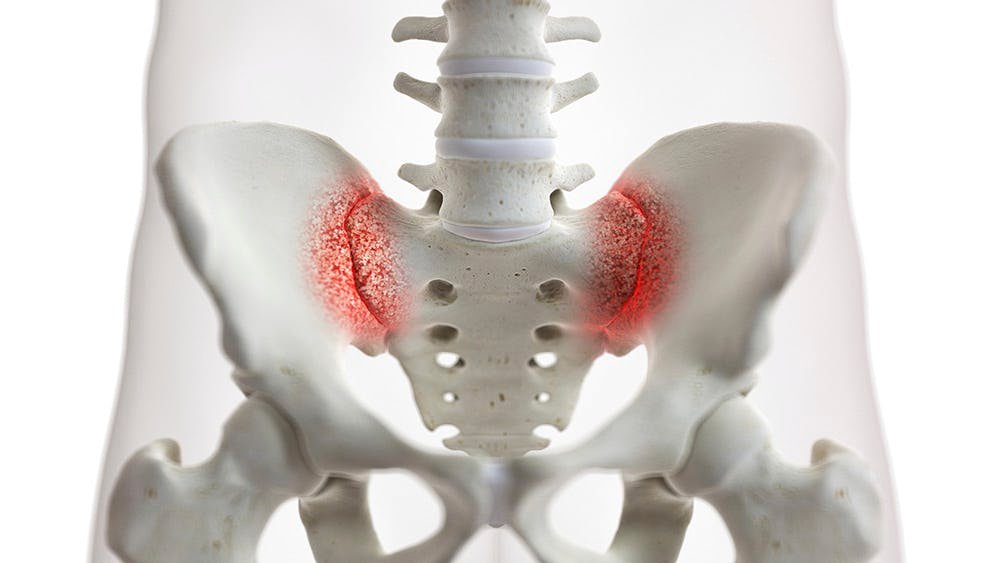

Sacroiliac Joint Disease

The sacroiliac joint (SI joint) is located between the sacrum and the ilium bones of the pelvis. Dysfunction in the SI joint can lead to localized pain in the lower back, often aggravated by prolonged sitting, walking, or climbing stairs. Conservative treatments include physical therapy, SI joint injections, and stabilization exercises.